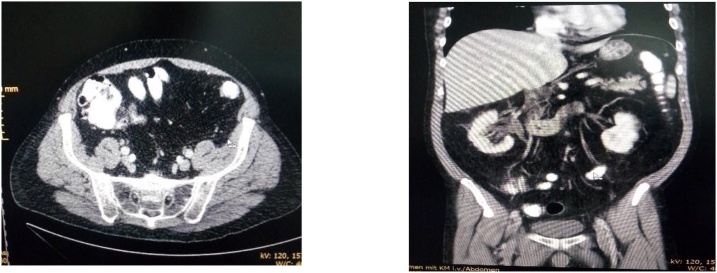

The abdomen was soft with bilateral lower quadrant tenderness, worse on the right than on the left side. The leukocyte count was 14 × 109/L The computed tomography CT with intravenous und rectal contrast shows the full length of a distended appendix, appendiceal wall thickening with enhancement, periappendiceal free fluid, findings that indicate appendicitis (Fig. 1Fig. 1,2). Diverticula of the sigmoid colon was highlighted, but without signs of inflammation.

Fig. 1,2.

Abdominal computed tomography demonstrating enlarged appendix in diameter and periappendiceal free fluid..